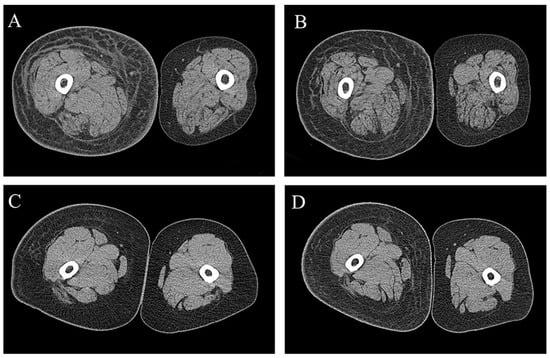

2.3. CT-Based Quantitative Measurement of Lymphedema